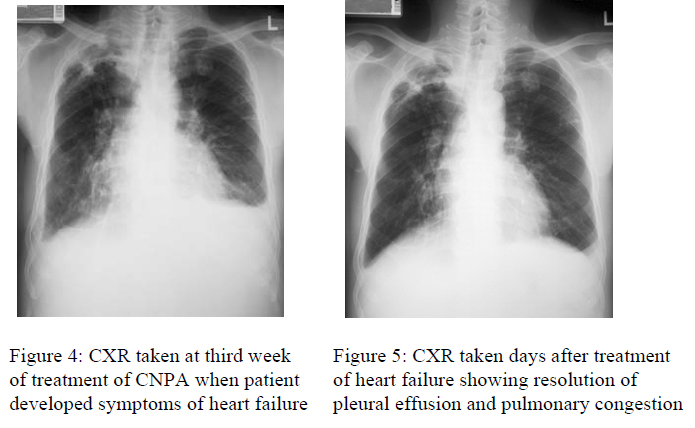

Three weeks later, he complained of gradual worsening of shortness of breath on exertion. Exercise capacity had reduced to only 1 flight from 3 flights of stairs. Orthopnea, ankle and genitalia swelling were noted. There was no chest pain, cough, gastrointestinal upset or fever.

Physical examination revealed abnormally raised blood pressure up to 160/80 mmHg, raised jugular venous pressure, bilateral pitting ankle edema, and weight gain of 3 kg. Heart sounds were normal, no murmur was detected. Percussion dullness & inspiratory crackles were detected over both lung bases. ECG did not reveal any abnormality.

Routine blood tests were unremarkable. There was no renal function deterioration. Inflammatory markers had improved.

CXR showed bilateral pleural effusion, upper lobe diversion, Kerley’s lines [Fig 4]. The initial right upper zone changes had improved. A transudate was yield on tapping of the left pleural effusion. Echocardiography showed LVEF 55%, no focal hypokinesia, just mild mitral regurgitation and trivial tricuspid regurgitation. Coronary angiogram was normal.

He was treated as congestive cardiac failure (CHF) with diuretic. Repeated chest X-ray showed prompt resolution of the pulmonary congestion [Fig. 5]. In view of the temporal relationship of the CHF with itraconazole therapy, the drug was changed to voriconazole. After that, there was no recurrence of heart failure even without additional medications. The sputum for fungal culture showed persistent conversion from the 3rd months of therapy onwards.